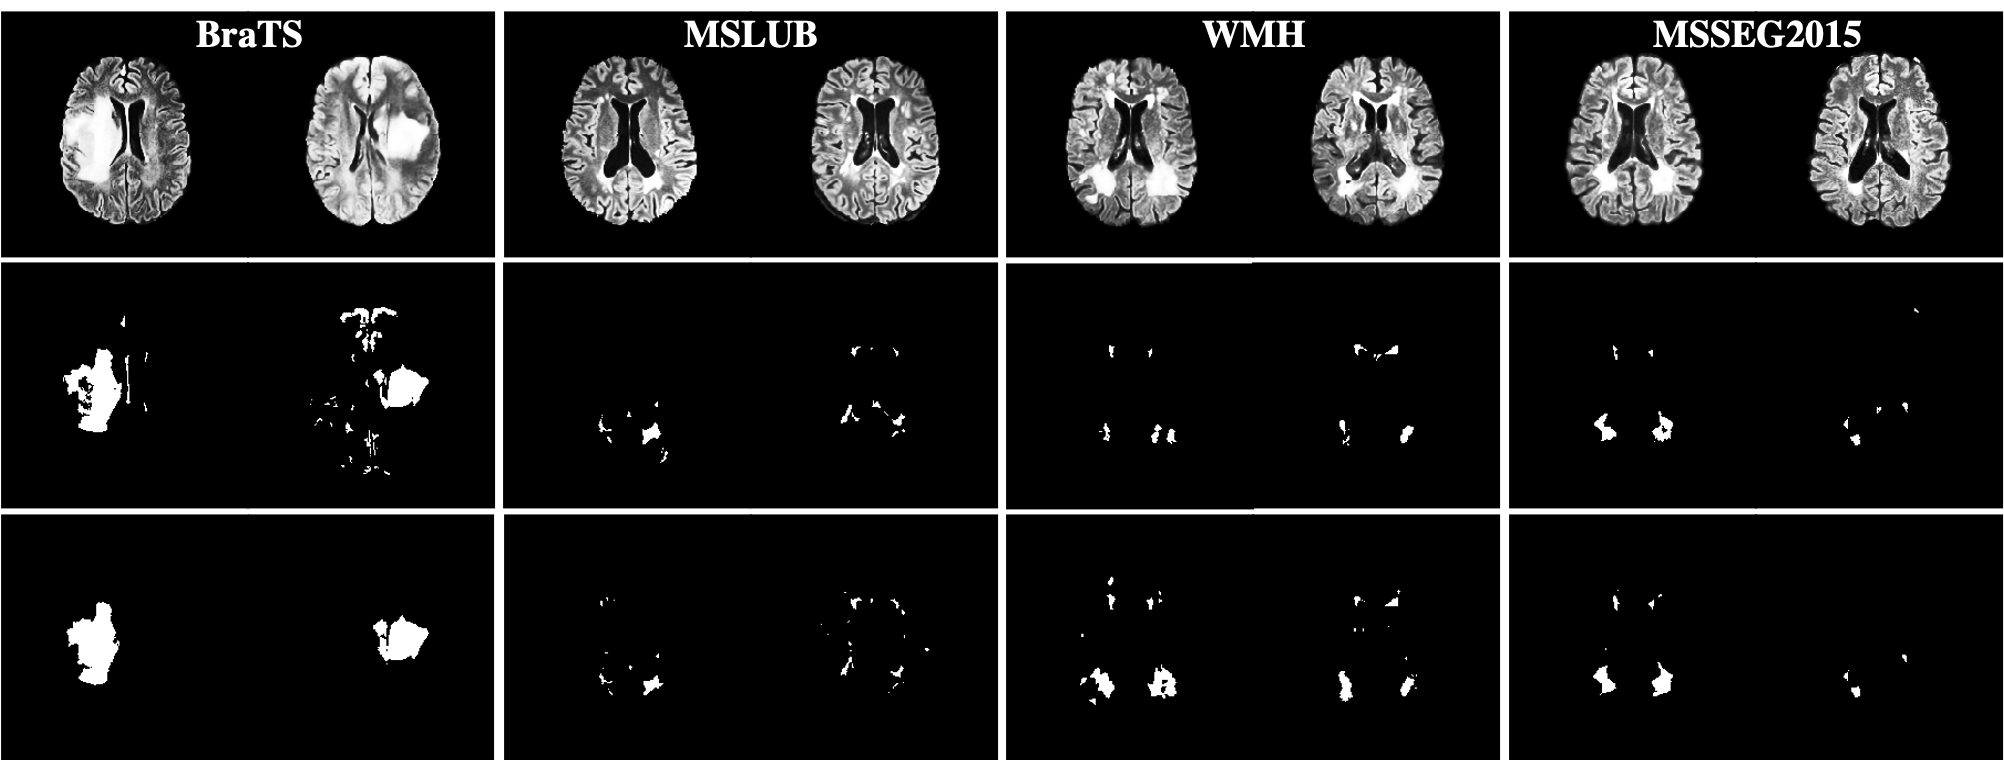

Figure 3 shows the qualitative results of our proposed baseline. The visual segmentation quality based on image-hyperintensities is decent and shows the approximate localization of anomalies.

We also present the quantitative results of the two experiment settings for all data sets using all metrics in table 4. In experiment one, our proposed method performs best on the BraTS data set which has the largest anomalies, and worst on MSLUB with the smallest anomalies. This can partly be attributed to our post-processing where we discard connected components with less than 20 voxels. Datasets with smaller anomalies are more affected by this. Also in experiment two, BraTS is the data set with the highest DSC and AUPRC.